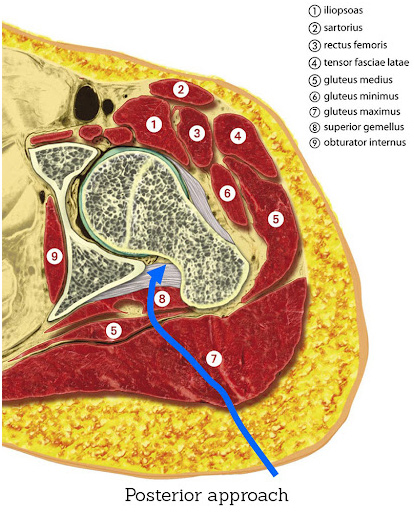

Posterior Approach

The posterior approach is performed through an incision at the back of the hip provides excellent visibility of the acetabulum (hip socket) and the femur, making it useful in complex cases or revision surgeries. This technique involves detaching some of the short external rotators to access the joint, which are re-attached at the end of the procedure.

A smaller incision (mini-posterior approach), is often sufficient to perform this approach.

POSTERIOR APPROACH – The posterior approach is performed through an incision at the back of the hip provides excellent visibility of the acetabulum (hip socket) and the femur, making it useful in complex cases or revision surgeries. This technique involves detaching some of the short external rotators to access the joint, which are re-attached at the end of the procedure.

Posterior Approach Potential Advantages:

- Familiarity: Many surgeons are trained in this approach, making it widely available.

- Joint Visibility: The posterior approach provides excellent visibility of the hip joint, which can be beneficial in some complex revision cases.

Posterior Approach Potential Considerations:

- Muscle Damage: The approach involves cutting through major muscles at the back of the hip, which can lead to longer initial recovery periods and greater post-operative pain.

- Risk of Dislocation: There’s a slightly higher risk of hip dislocation after surgery, necessitating more precautions during the recovery period.

- Longer Recovery: Patients may take longer to return to certain activities, with more restrictions on movement to prevent dislocation.

Posterior Approach Post-Op Precautions:

Posterior Approach Post-op precautions are very restrictive and usually include the following:

- Avoid the combined movement of bending your hip and turning in your foot.

- You should sleep with a pillow between your legs for 6 weeks.

- Avoid crossing your legs and bending your hip past a right angle.

- Avoid low chairs.

- Avoid bending over to pick things up. Grabbers are helpful as are shoehorns or slip on shoes.

- An elevated toilet seat should be used.